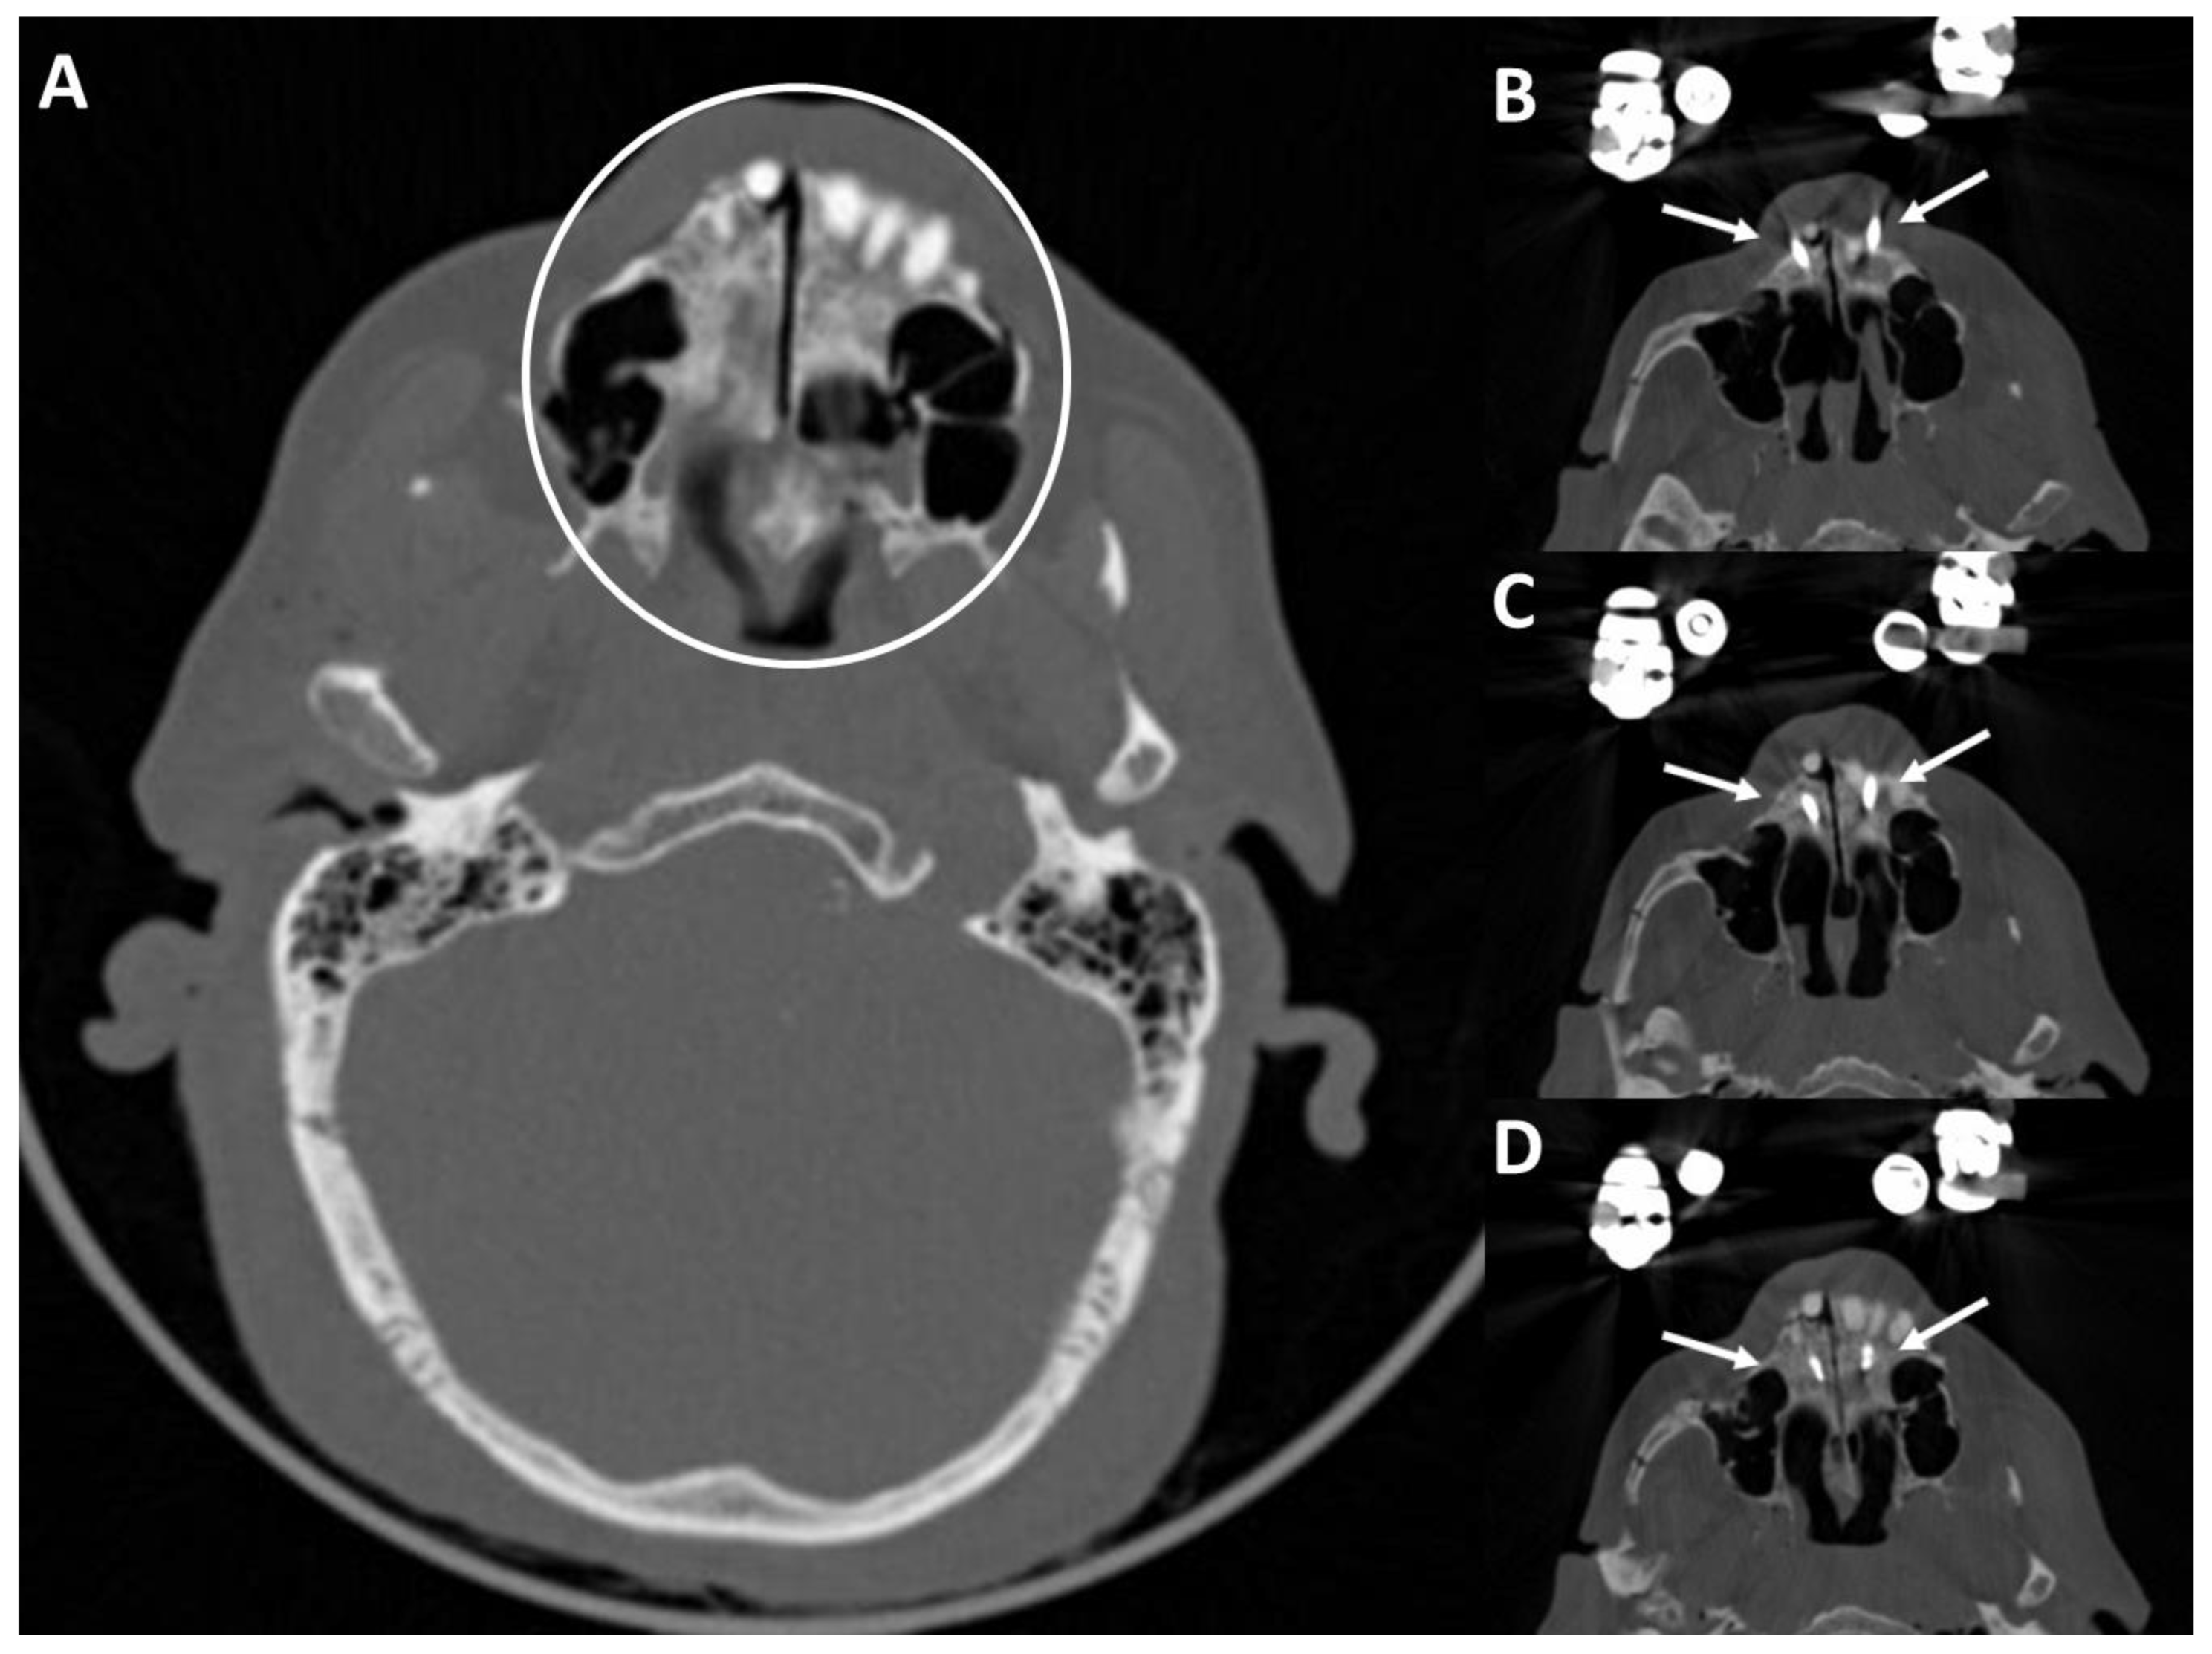

3.4. Postoperative Results in the CT Scans

4.2. Post-Operative CT Scans